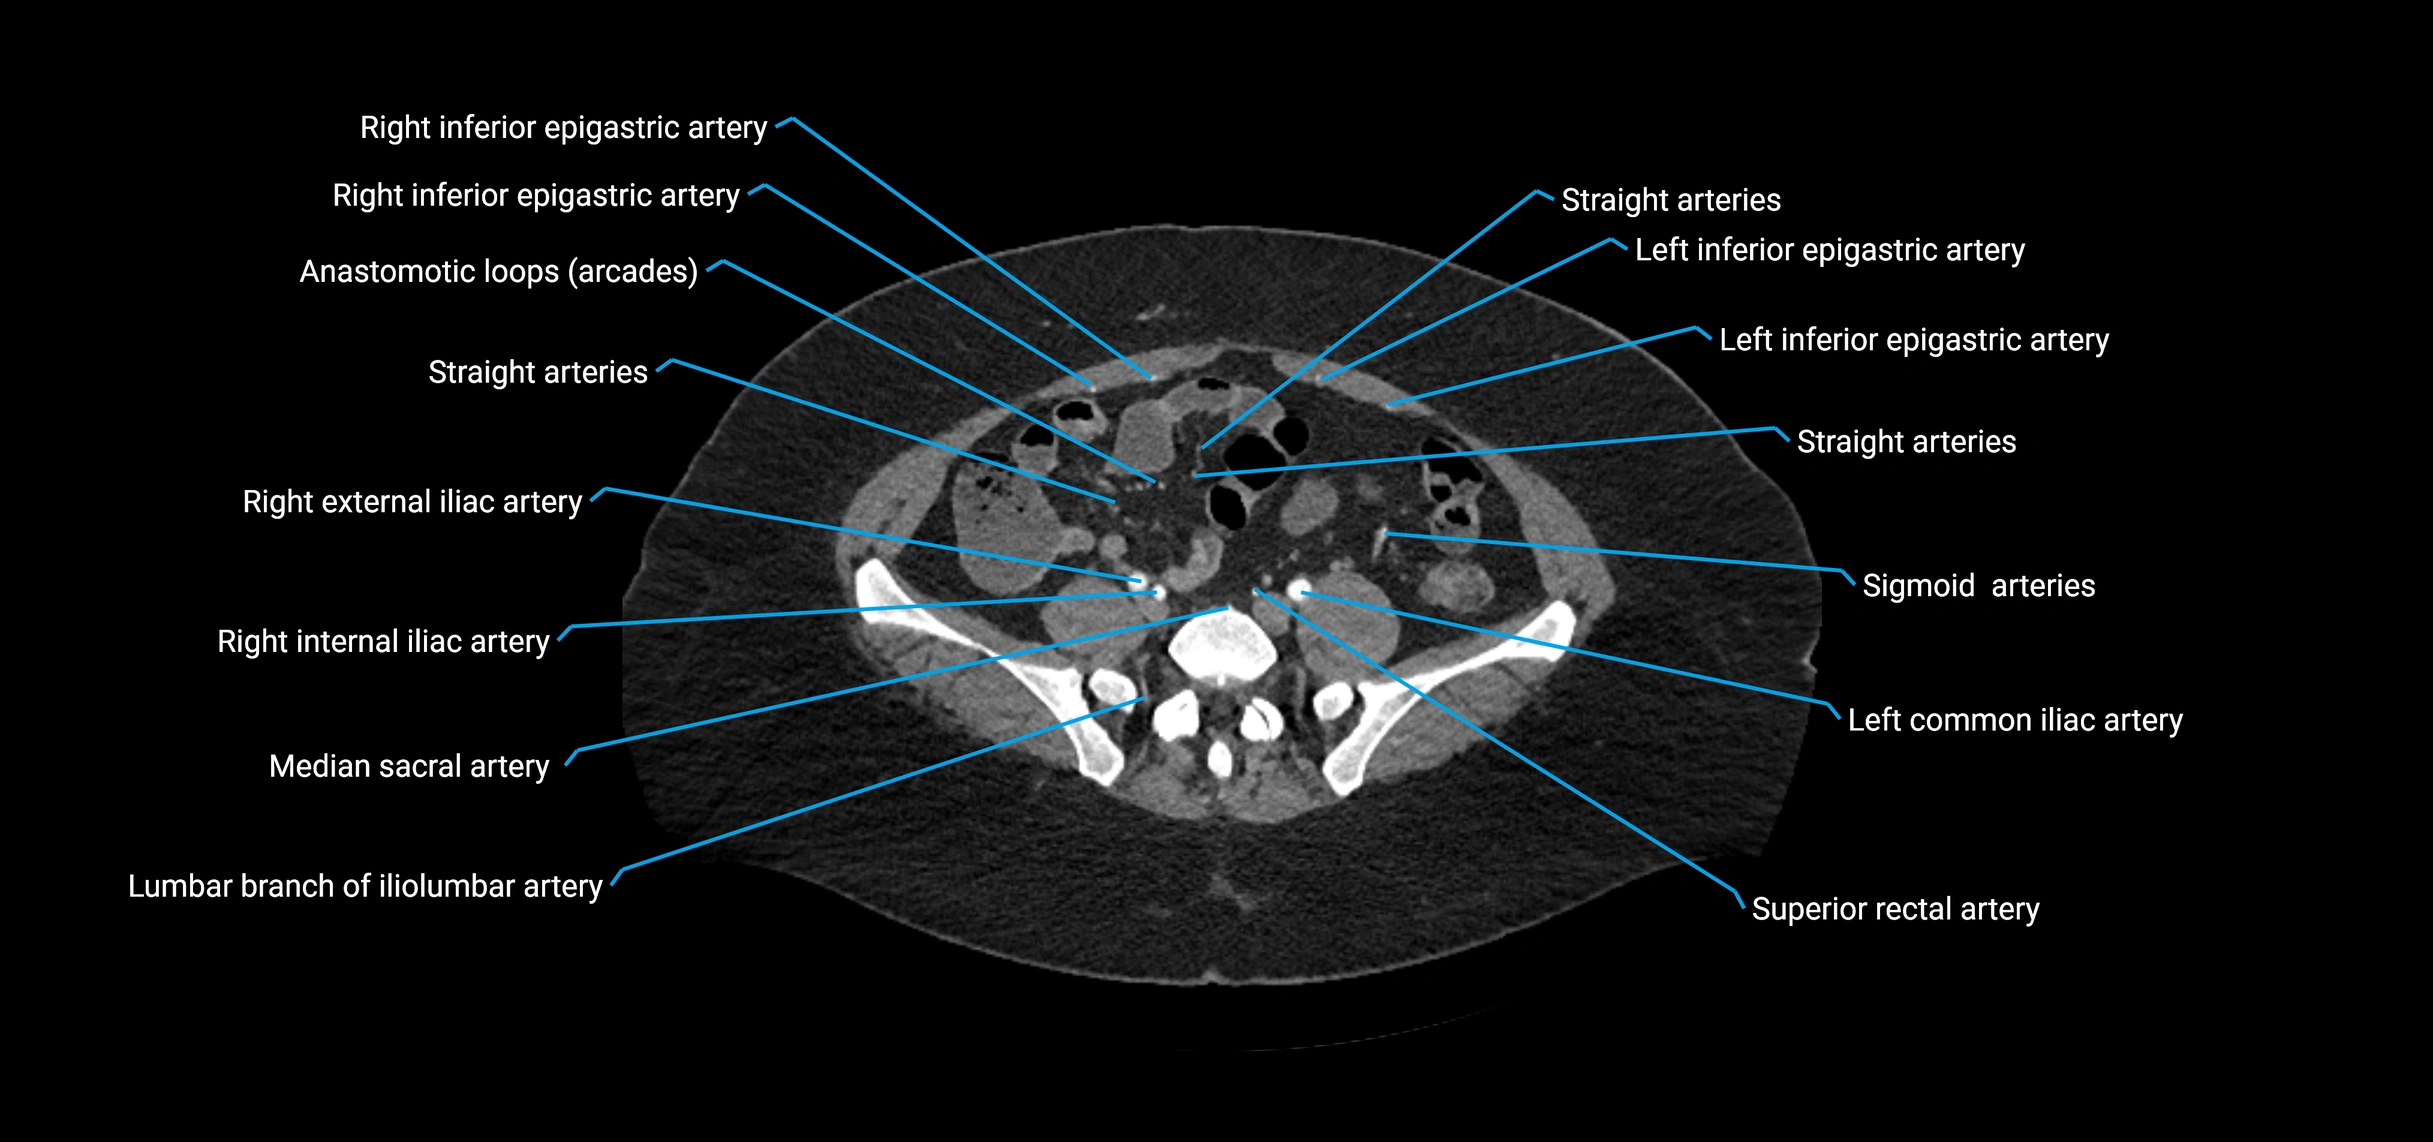

Contrast-enhanced CT (CTA):

• Gold standard for abdominal aortic imaging

• Provides excellent detail of lumen, wall, aneurysm, thrombus, and branch vessels

• Multiplanar and 3D reconstructions help in aneurysm measurement, stent graft planning, and dissection evaluation